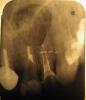

Резекция была проведена, кисту удалили, полость бывшей кисты заполнили костным веществом, положили мембрану. Ретроградное пломбирование не проводилось, насколько я слышала и ощущала.Снимок после операции забрал себе "для истории работ" (цитирую) хирург. Швы сняли через штифт под коронку устанавлявать сразу не стали, решили подождать, как все приживетсяотправили на 3 недели гулять. Прошел месяц был сделан снимок (№3 в другой клинике)post-17593-1297810247_thumb.jpg и что увидели...в канале 2-го зуба отсутствует пломбир.материал и при прохожденнии на верхушке - чувствительность (т.е как я понимаю, канал открыт, сообщается с полостью бывшей кисты.

3) не кажется ли вам что резерцированный корень слишком короткий и не подлежит дальнейшему протезированию?